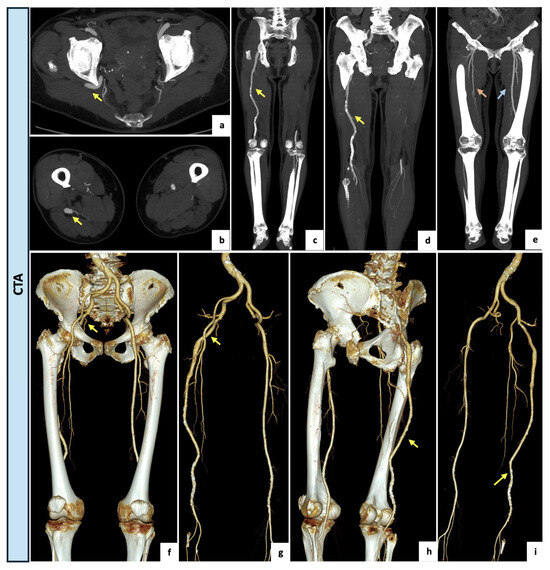

2.2. Case 2

The next patient was a healthy 53-year-old male referred to the Vascular Surgery Department of our center for critical ischemia with rest pain of the right lower limb. Upon physical examination, stable vital signs, palpable and symmetric femoral pulses, absent right popliteal and pedal pulses and mild hypothermia of the right foot were detected. Neurological examination revealed no motor or sensory deficit. The CTA examination (Figure 3) showed a right aneurysmatic complete PSA (23 mm in the maximal caliber) with extensive luminal thrombus originating from the internal iliac artery. The right external iliac artery was hypoplastic, probably due to a steal syndrome caused by the PSA. The ipsilateral SFA appeared incomplete and noticeably reduced in caliber (type 2a). A thrombotic occlusion of the left popliteal artery and left tibio-peroneal trunk tibial axis with filling thrombotic defects at the anterior tibial artery were observed. The posterior tibial and peroneal arteries were patent. The case was collegially discussed, and a hybrid approach was preferred. Firstly, a right femoro-tibial bypass with the anterior tibial as the target artery was performed under general anesthesia using the ipsilateral great saphenous vein in a reversed fashion. After two days, the patient subsequently underwent endovascular embolization of the aneurysmal PSA. The procedure was performed in our angiographic suite. A left femoral access was obtained under local anesthesia. The sciatic artery was catheterized and embolized using a 12 mm Amplatzer Vascular Plug II (Abbott Medical, North Plymouth, MN, USA) deployed immediately distally to the internal pudendal artery origin. Both of the procedures were conducted without complications. At the 3-month CTA follow-up examination, the bypass was patent, and the aneurysm was completely excluded.

Figure 3.

(a,b) VR reconstruction of the preoperative CTA showing a right complete PSA originating from the internal iliac artery (arrow). The right external iliac artery appears hypoplasic and the SFA appears incomplete and diminished in caliber (type 2a). (c) Axial view showing an aneurysmal dilatation (23 mm) of the PSA with luminal thrombus (arrow). A hybrid approach was preferred, with the first step consisting of a left femoro-tibial bypass with the anterior tibial as the target artery. (d–f) Selective angiographic images preliminary to the endovascular step showing a patent femoro-tibial bypass. (g–j) After a contralateral 6F-sheat femoral access, the aneurysmal PSA was selectively catheterized and completely embolized using a 12 mm Amplatzer Vascular Plug II (arrowhead) deployed immediately distally to the internal pudendal artery origin. (k–n) VR reconstructions of the postoperative CTA (3-month) demonstrating the patent femoro-tibial bypass with complete exclusion of the aneurysmal PSA (arrows).